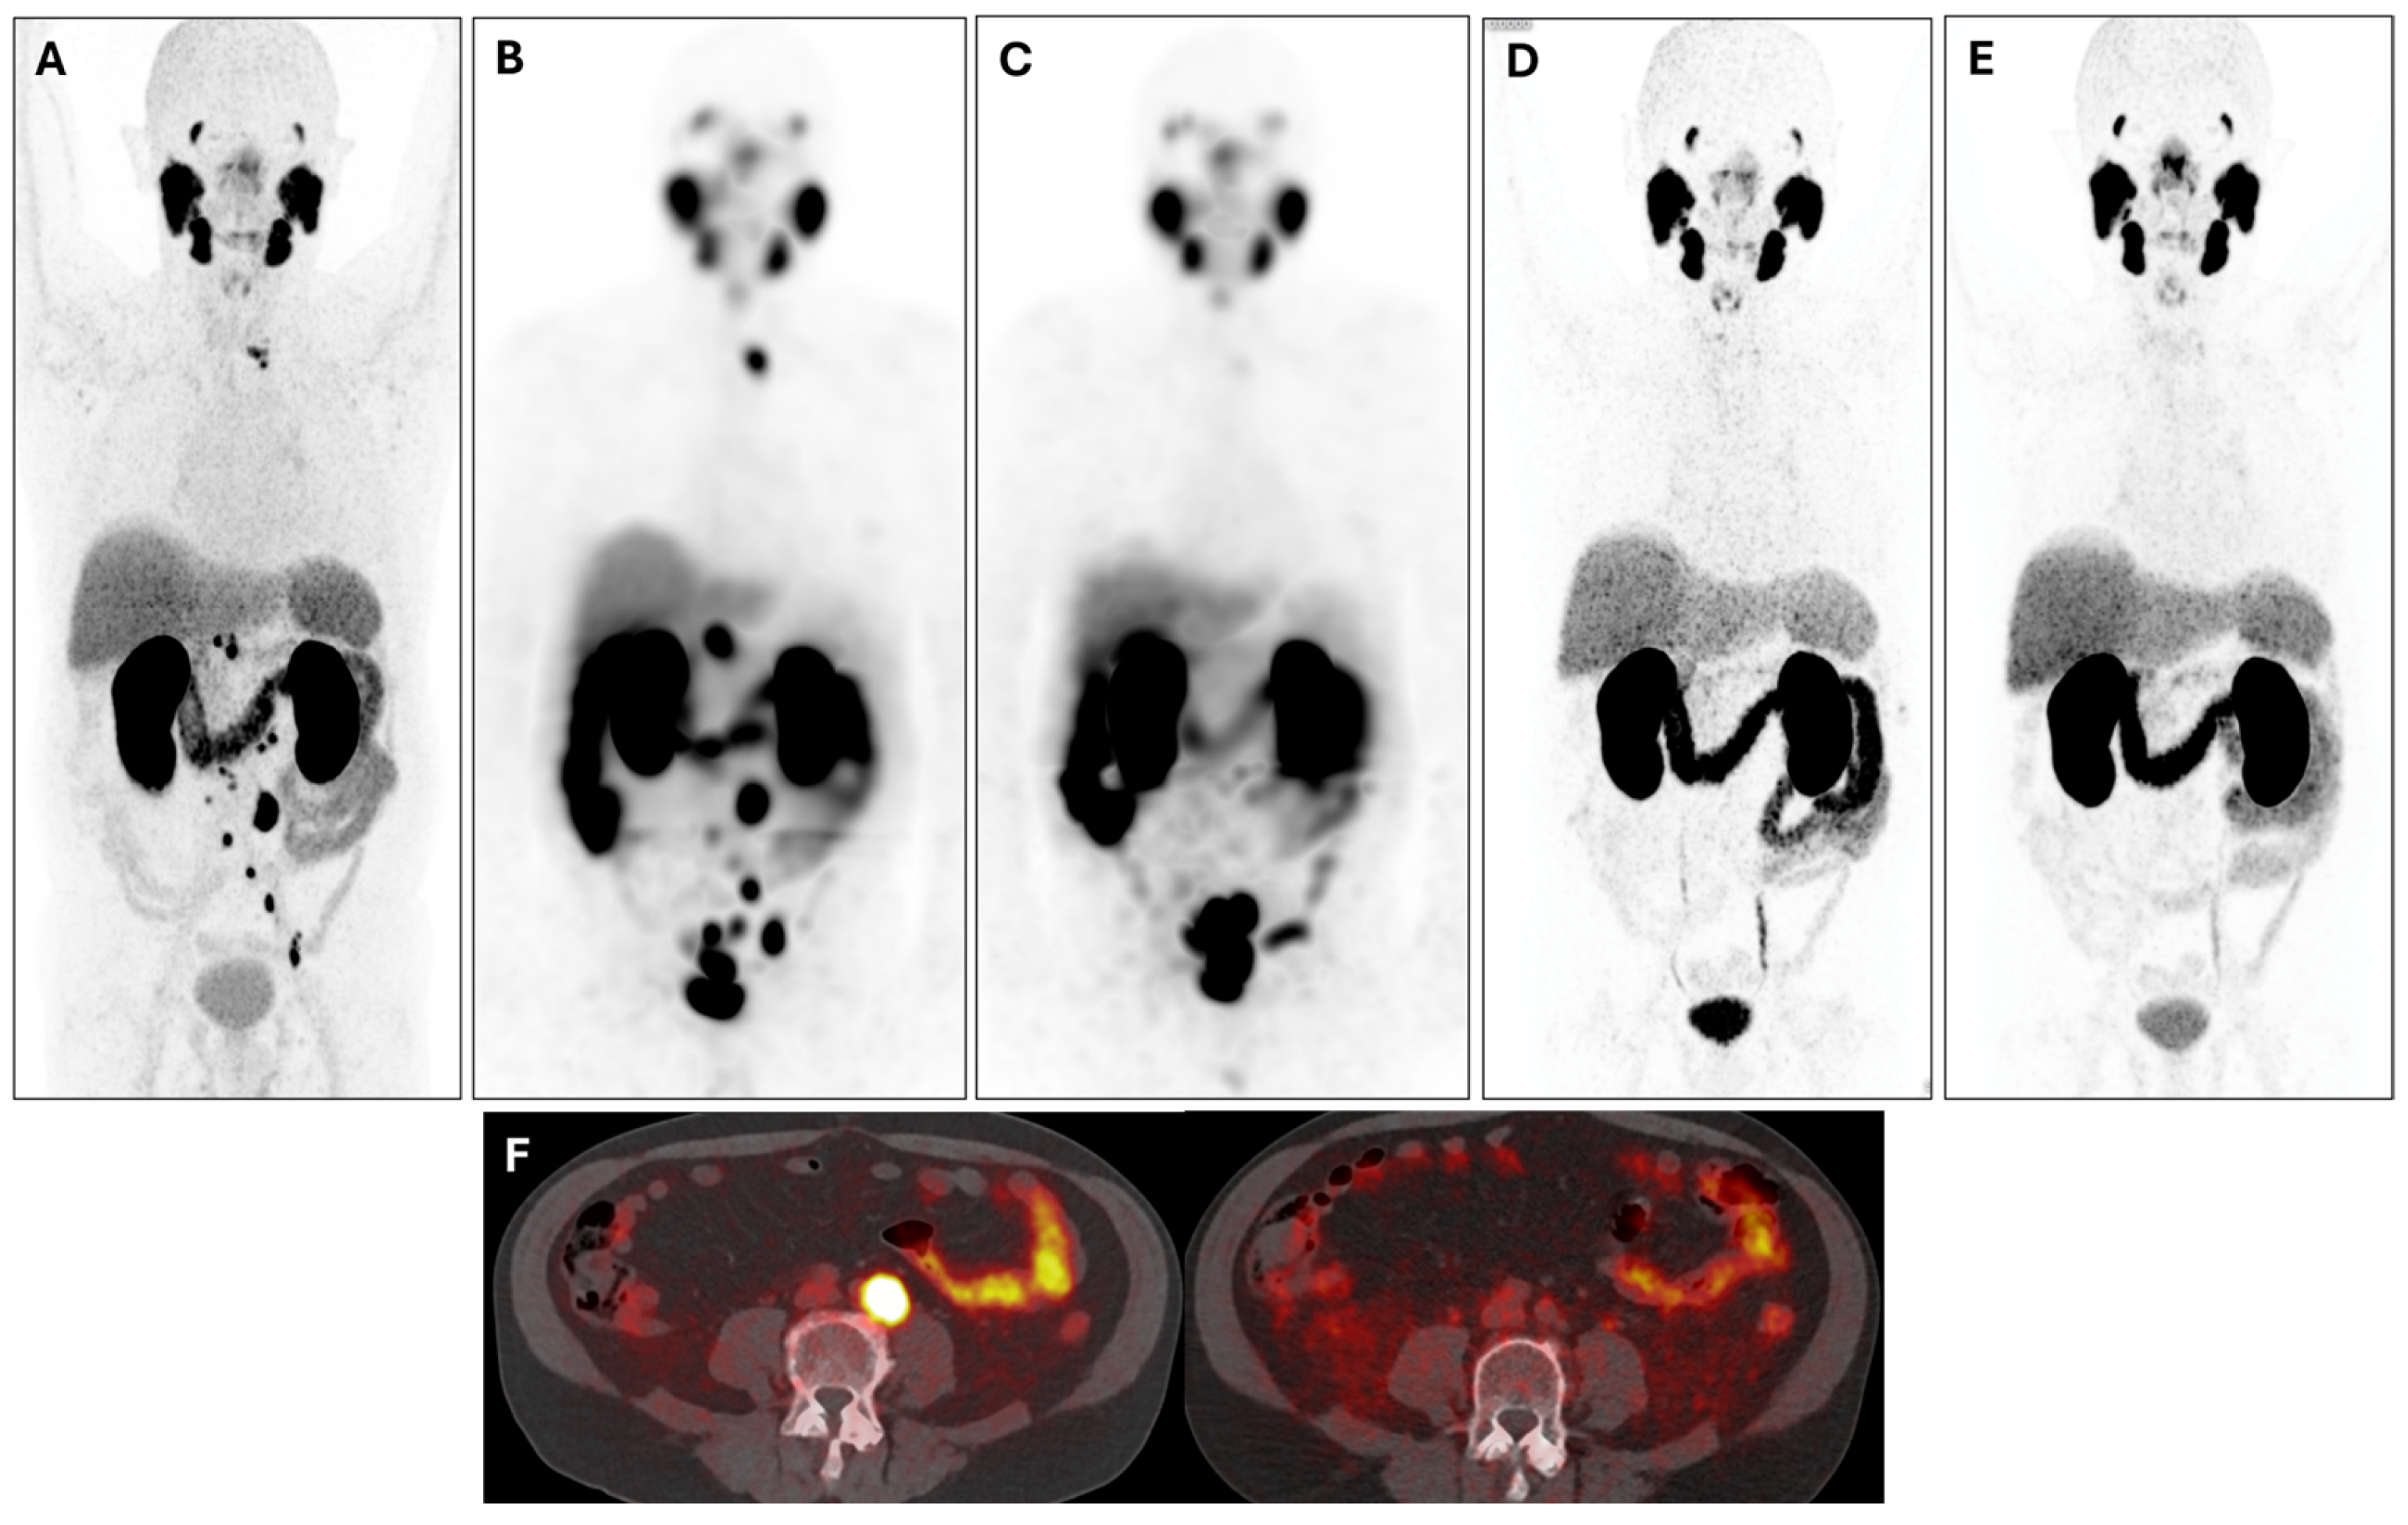

3. Results